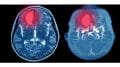

Acute Vestibular Symptoms: an Approach to Diagnosis and Management

Summary Acute vestibular symptoms include manifestations like vertigo, dizziness, lightheadedness, and unsteadiness, among others. They are a common concern in patients presenting to the acute…